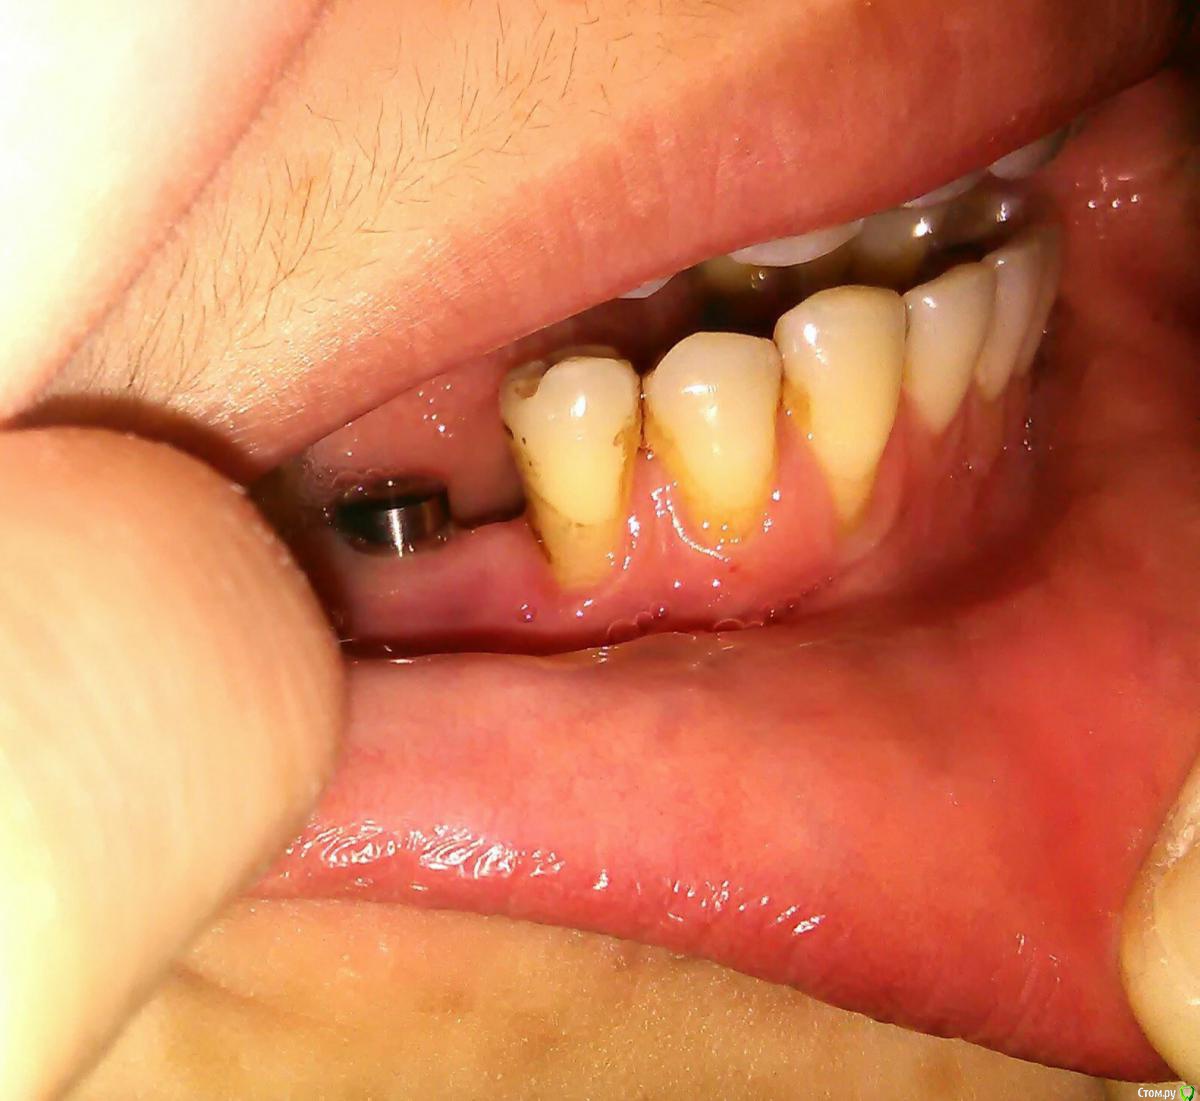

akburan Опубликовано 8 февраля, 2017 Поделиться Опубликовано 8 февраля, 2017 Установили имплант 3 мес. назад. Имплант прижился.Одновременно с имплантацией провели синус-лифтинг. До операций имела также место рецессия десны. Но через 3 недели после установки и подсадки костн. материала десна опустилась еще ниже в области импланта и 3.5 зуба, из-за чего мне кажется, что внедрили мало костного материала. С этой жалобой обращалась к хирургу неоднократно, на что он отвечал что все хорошо и десна со временем САМА восстановится. В данный момент уже сняли слепки для дальнейшего протезирования, но мне состояние десны категорически не нравится и я хочу что-то с этим сделать. Можно ли восстановить десну в обл. импланта? Возможно ли не извлекать при этом имплант? Поможет ли лоскутная операция в том смысле, что прирастет ли лоскут к импланту? Ссылка на комментарий

Доктор Добрых Дел Опубликовано 8 февраля, 2017 Поделиться Опубликовано 8 февраля, 2017 Я бы рекомендовал Вам закрыть рецессии (оголенные корни) в области 43,44,45 зубов. 1 Ссылка на комментарий

akburan Опубликовано 9 февраля, 2017 Автор Поделиться Опубликовано 9 февраля, 2017 а что вам не нравится? Платформа имплантата не видна, по высоте десна есть. Объем?Не нравится то как нарастили кость или лучше сказать недорастили, мне кажется недоложили костного материала, а также десна у основания соседнего зуба, там до этого она не была так опущена и зуб начал пошатываться. Я бы рекомендовал Вам закрыть рецессии (оголенные корни) в области 43,44,45 зубов.Это тоже в планах, а вот как быть с имплантом, возможно ли у его основания уже после протезирования приподнять десну тоже? Ссылка на комментарий

DrNice Опубликовано 9 февраля, 2017 Поделиться Опубликовано 9 февраля, 2017 Не нравится то как нарастили кость или лучше сказать недорастили, мне кажется недоложили костного материала, а также десна у основания соседнего зуба, там до этого она не была так опущена и зуб начал пошатываться. Это тоже в планах, а вот как быть с имплантом, возможно ли у его основания уже после протезирования приподнять десну тоже? Десну приподнять можно, но я опять повторюсь, мне не нравится кость вокруг имплантата. Ссылка на комментарий

Oscar Опубликовано 13 марта, 2017 Поделиться Опубликовано 13 марта, 2017 Объем десны можно добавить, но основная проблема резорбция костной ткани в верхней трети импланта, кстати что за система? Израиль? Ссылка на комментарий